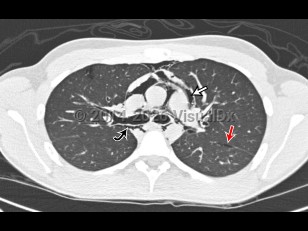

Chest pain, Dyspnea, 50-59 year old Female

Pulmonary embolismPulmonary embolism